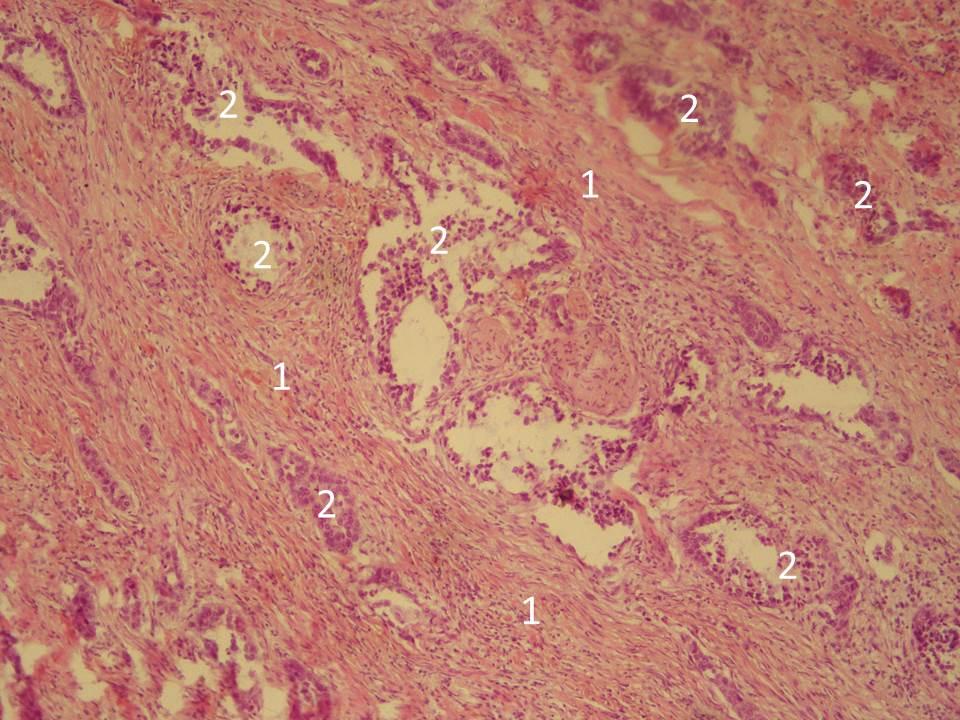

Микроскопический взгляд на мишитарный туберкулез легкого: фотодокументация

Раздел: Снимки-откровения